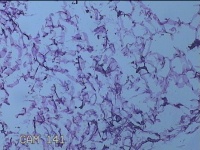

外阴部包块

性别

女

年龄

37岁

临床诊断

皮脂腺囊肿

一般病史

外阴部起包块一月余。

标本名称

大体所见

灰白暗红色包块2.3x1.8x0.8cm一个,表面糜烂,切开包块呈实性,切面灰白淡黄色,质软。

有那么点像脂肪瘤。